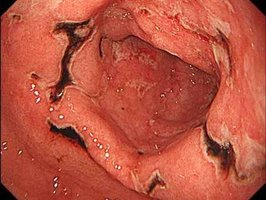

潰瘍の数で単発性潰瘍と多発性潰瘍があり、NSAIDs潰瘍では多発性が多くみられます。また発症様式には急性胃潰瘍と慢性胃潰瘍があります=画像=。急性胃潰瘍は急性胃粘膜病変(AGML)とも呼ばれ、慢性胃潰瘍に比べて発病がより突然で激痛です。なお、一般的に胃潰瘍は慢性胃潰瘍のことです。